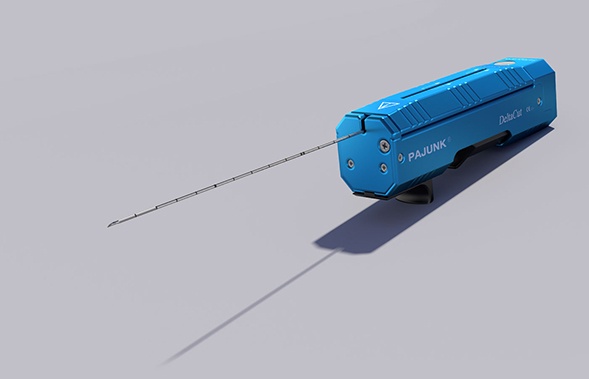

- Dụng cụ (dạng súng) sinh thiết u mô: U vú, u gan, u phổi, u tuyến giáp...